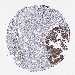

OVARIAN CANCER - Protein expressioni

A mouse-over function shows sample information and annotation data. Click on an image to view it in a full screen mode. Samples can be filtered based on level of antibody staining by selecting one or several of the following categories: high, medium, low and not detected. The assay and annotation is described here.

Note that samples used for immunohistochemistry by the Human Protein Atlas do not correspond to samples in the TCGA dataset.

Antibody stainingi

Antibody staining in the annotated cell types in the current human tissue is reported as not detected, low, medium, or high, based on conventional immunohistochemistry profiling in selected tissues. This score is based on the combination of the staining intensity and fraction of stained cells.

Each image is clickable and will lead to virtual microscopy that enables deeper exploration of all samples and also displays staining intensity scores, fraction scores and subcellular localization as well as patient and tissue information for each sample.

Antibody HPA038122

Staining

High

Medium

Low

Not detected

Intensity

Strong

Moderate

Weak

Negative

Quantity

>75%

75%-25%

<25%

None

Location

Nuclear

Cytoplasmic/membranous

Cytoplasmic/membranous,nuclear

Cystadenocarcinoma, serous, NOS

Carcinoma, endometroid

Cystadenocarcinoma, mucinous, NOS

Carcinoma, NOS